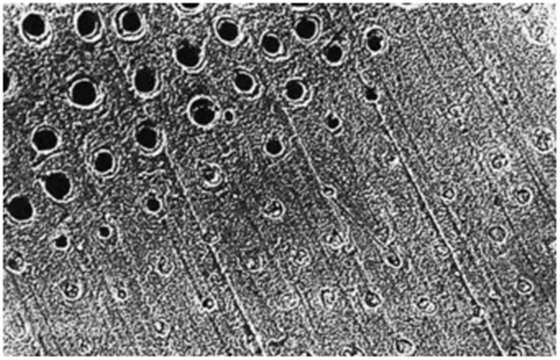

牙本質(zhì)切削后牙本質(zhì)縱斷面,可見牙本質(zhì)小管中存在玷污層栓(放大倍數(shù)2000)

圖中上半部分牙本質(zhì)采用37%磷酸酸蝕15秒徹底沖洗后牙本質(zhì)橫斷面,可見玷污層已經(jīng)被去除(放大倍數(shù)1000)